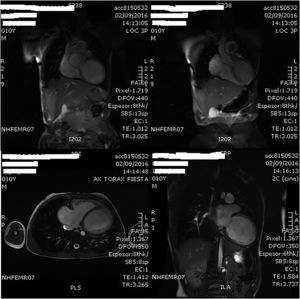

A los 10 años es ingresado en nuestro centro por cuadro de astenia y pérdida ponderal de un mes de evolución junto a franco deterioro de su clase funcional, sin intercurrentes acompañantes. Analíticamente destacaba un PRO-BNP de 27.703pg/ml, y a nivel ecocardiográfico a los hallazgos conocidos se añadía un ventrículo izquierdo (VI) ligeramente dilatado, pero con disfunción sistólica severa. El estudio se completó mediante cardio-RMN que mostró ausencia de alteraciones de la perfusión miocárdica con el VI severamente dilatado (IVTDVI: 176ml/my) con hipocinesia generalizada y FE del 18% (fig. 1); ventrículo derecho (VD) severamente dilatado (IVTDVD: 154ml/my) con FE del 34% (fig. 2). Se estableció el diagnóstico de miocardiopatía idiopática con disfunción grave del VI en paciente con insuficiencia valvular pulmonar severa post-debanding, y se inició tratamiento médico (captopril, espironolactona, furosemida, Lanacordin® y carvedilol). En sucesivos controles el paciente se encontró clínicamente estable con aceptable capacidad funcional, completándose el estudio mediante cateterismo cardiaco que confirmó los hallazgos de la cardio-RMN detectando una hipertensión pulmonar ligera (PsAP: 32mmHg), un índice de resistencias pulmonares de 2,02UW/my y un árbol coronario normal.